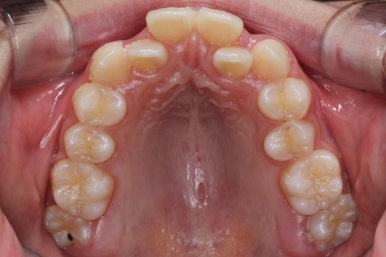

처음 내원 때의 입안 모습입니다.

영구치는 모두 맹출이 되어있었고 아랫니는 윗니에 비해 매우 가지런한 편이였습니다.

윗니 중에서도 앞니가 매우 삐뚤하고 특히 작은 앞니 양쪽 모두가 아래 앞니보다 안쪽에 들어가 있는 모습입니다.

이번 환자분은 송곳니가 거의 자기위치에 나오게 되면서 약한 작은 앞니를 밀어낸 경우입니다.

송곳니는 거의 제자리에 나오긴 했지만 작은 앞니가 안쪽으로 쏙 들어가 있기 대문에 상대적으로 덧니처럼 보이게 되는 것입니다.